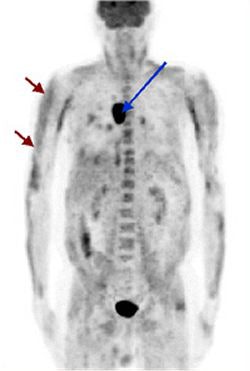

| A patient diagnosed with dermatomyositis (shown by the red arrows) also exhibits bronchogenic carcinoma (shown by the blue arrow) on a screening PET scan. Image courtesy of the Society of Nuclear Medicine and the Hospital of Johann Wolfgang-Goethe University. |

Over the course of five years, the team evaluated 30 patients (17 males and 13 females averaging 55 years old) with suspected PS. Diagnoses on the patients ranged from cerebellar degeneration, erythrodermia, dermatomyositis, polneuropathia, and others.

PET scans were conducted and reviewed for convincing signs of malignant metabolism, and the results were compared to histopathologic, radiologic, and follow-up data. The group detected underlying malignancy in 8 patients, of which PET found 7 of the 8 malignant neoplasms. On the basis of cost and time needed to diagnose the malignancies with conventional tools, the group said it found F-18-FDG-PET to be of reasonable value as a screening tool in suspected PS.